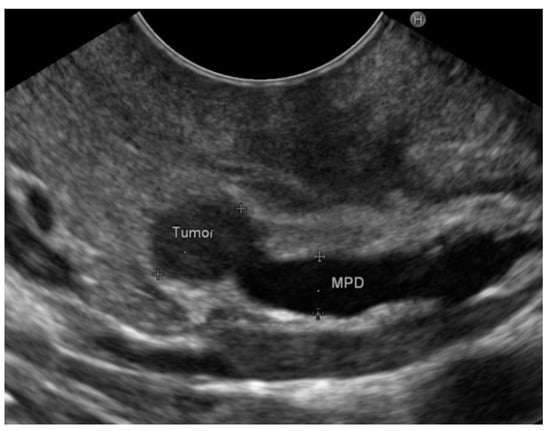

3.2. EUS Findings

3.3. Final Diagnoses